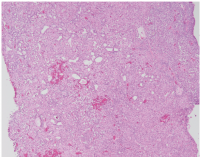

A punch biopsy was performed. Histopathologic evaluation showed a well-circumscribed solid-cystic dermal tumor consisting of a solid sheet-like arrangement of eosinophilic, polyhedral and clear cells. The tubular and cystic structures are filled with homogeneous eosinophilic material. Atypia, invasion, necrosis, and mitoses are not observed (Figs. 2–3). Immunohistochemical studies showed tumor cells positive for cytokeratin 7 (CK7) and epithelial membrane antigen (EMA), and negative for renal cell carcinoma marker (RCC), paired box gene 8 (PAX8), carcino-embryonic antigen (CEA), and CD10. Tumor cells were also diffusely positive by periodic acid schiff (PAS) stain. These findings were consistent with nodular hidradenoma.

Fig. 2. The well-circumscribed dermal tumor consists of a solid sheet-like arrangement, containing eosinophilic, polygonal or fusiform cells, cystic spaces, and some cellular differentiation (Hematoxylin and eosin, 4x).